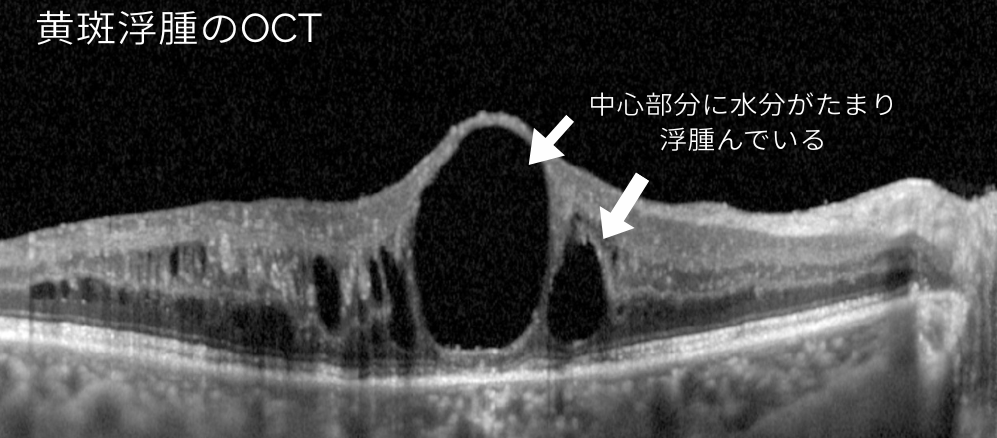

↑↑

糖尿病や静脈閉塞症などでみられる黄斑浮腫は、注射による治療(硝子体内注射)を行う場合があります。